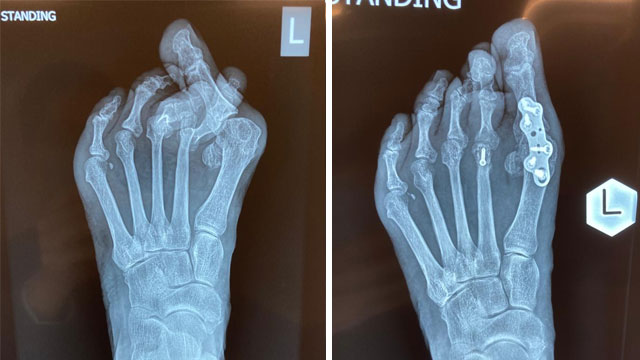

拇趾外翻是形容大拇指向外側移位,令大拇指第一關節腫大突出及發炎。成因可以是先天骨骼問題,或因後天的影響,例如長期穿著窄身或高跟鞋。

使用截骨方法來修正突出的骨頭,將拇指關節角度修復至正常狀態

* 將趾骨關節修復至正常狀態後,再以螺絲和鋼板融合,減低復發機會